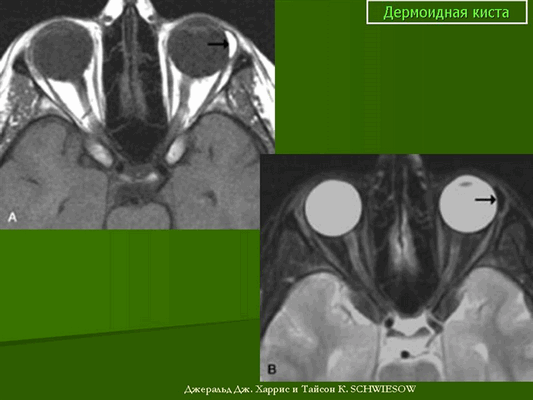

Наиболее детальную информацию о размерах, соотношении с прилежащими структурами, содержимом кистозного образования помогает оценить компьютерная или магнитно-резонансная томография (рис.2). В зависимости от содержимого кистозные образования орбит (плотности и содержания жирового компонента) на КТ и МРТ выглядят по-разному, не накапливают контрастный препарат, имеют четкие контуры и капсулу, в 15% случаев имеют кальцинаты (хорошо видны на КТ). МРТ и КТ необходимо для предоперационного планирования, чтобы полноценно оценить весь объём образования (иногда определяется и глубокий компонент, которым может быть источником рецидива).

МРТ орбит. Дополнительное тканевое образование с жировым компонентом (указано стрелочкой), гиперинтенсивное на Т1-ВИ (первое изображение), гипоинтенсивное на Т2-ВИ с жироподавлением (второе изображение), не накапливающее контрастный препарат Т1-ВИ с жироподавлением и контрастным усилением (последнее в ряду изображение).